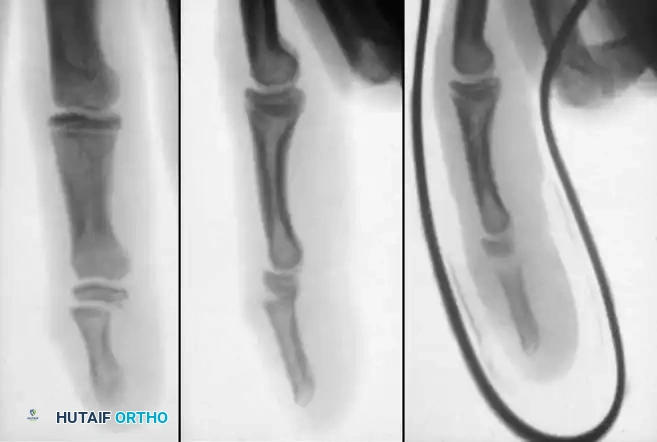

Distal Phalanx Fractures and Mallet Equivalents

Avulsion injuries of the distal phalanx and its physis frequently produce Salter-Harris type I or type III fractures.

Image

Adequate closed reduction of type I fractures generally yields satisfactory functional and radiographic outcomes. However, type III fractures of the distal phalanx produce a pediatric "mallet finger" equivalent.

In a young child, an accurate closed reduction followed by extension splinting is usually sufficient. If anatomical reduction cannot be obtained or maintained via closed means, open reduction and internal fixation (ORIF) are strictly indicated to restore the articular surface and terminal extensor tendon continuity.